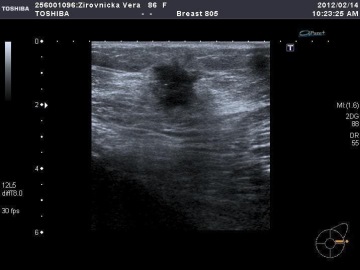

Snímek sonografie nádoru prsu.

„Sono” využívá schopnosti odrážet se v místech, kde se mění hustota tkáně. Na monitoru se pak různé tkáně a útvary zobrazují jako tmavší/světlejší. „Barvy” samy o sobě samozřejmě nemusejí nic znamenat, ale jedná se o jeden ze znaků, který pomáhá lékaři určit charakter vyšetřované tkáně. Ultrazvukem se dá vyšetřit mnoho struktur. Gynekolog jím vyšetřuje nejen tvoje vnitřní orgány jako dělohu a vaječníky, ale samozřejmě i průběh těhotenství, urolog zase stav močových cest a prostaty. V interně nebo chirurgii se využívá hojně ať už k vyšetření břišní dutiny nebo třeba cév. Sonem lze vyšetřit i prsa. Sonograficky nelze vyšetřit hluboké tkáně nebo kosti či plíce. Pozor – horší vyšetřitelnost je i u lidí s obezitou.

Vyšetření probíhá většinou opět vleže a opět si na něj budeš muset odložit oblečení. Lékař na tvoji kůži nanese gel, který umožňuje lepší přenos signálu, sedne si vedle tebe a postupně si prohlíží obrázky, které při vyšetřování ultrazvukovou sondou vznikají. Celé vyšetření by mělo být zcela nebolestivé a trvá několik minut.